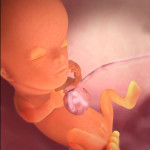

Tak wygląda płód w 11 tygodniu (klikalny):

USG w 11 tygodniu pokaże wyraźnie zarysy małego człowieka. Na wysokiej klasy sprzęcie ze szczególnie dobrą lokalizacją dziecka możesz już określić jego płeć. Jednak dane mogą być niedokładne.